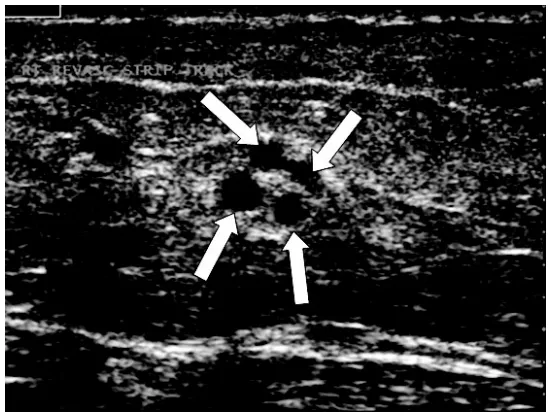

超声引导下经腔穿支静脉闭塞 (TRansluminal Occlusion of Perforators, TRLOP) 手术。